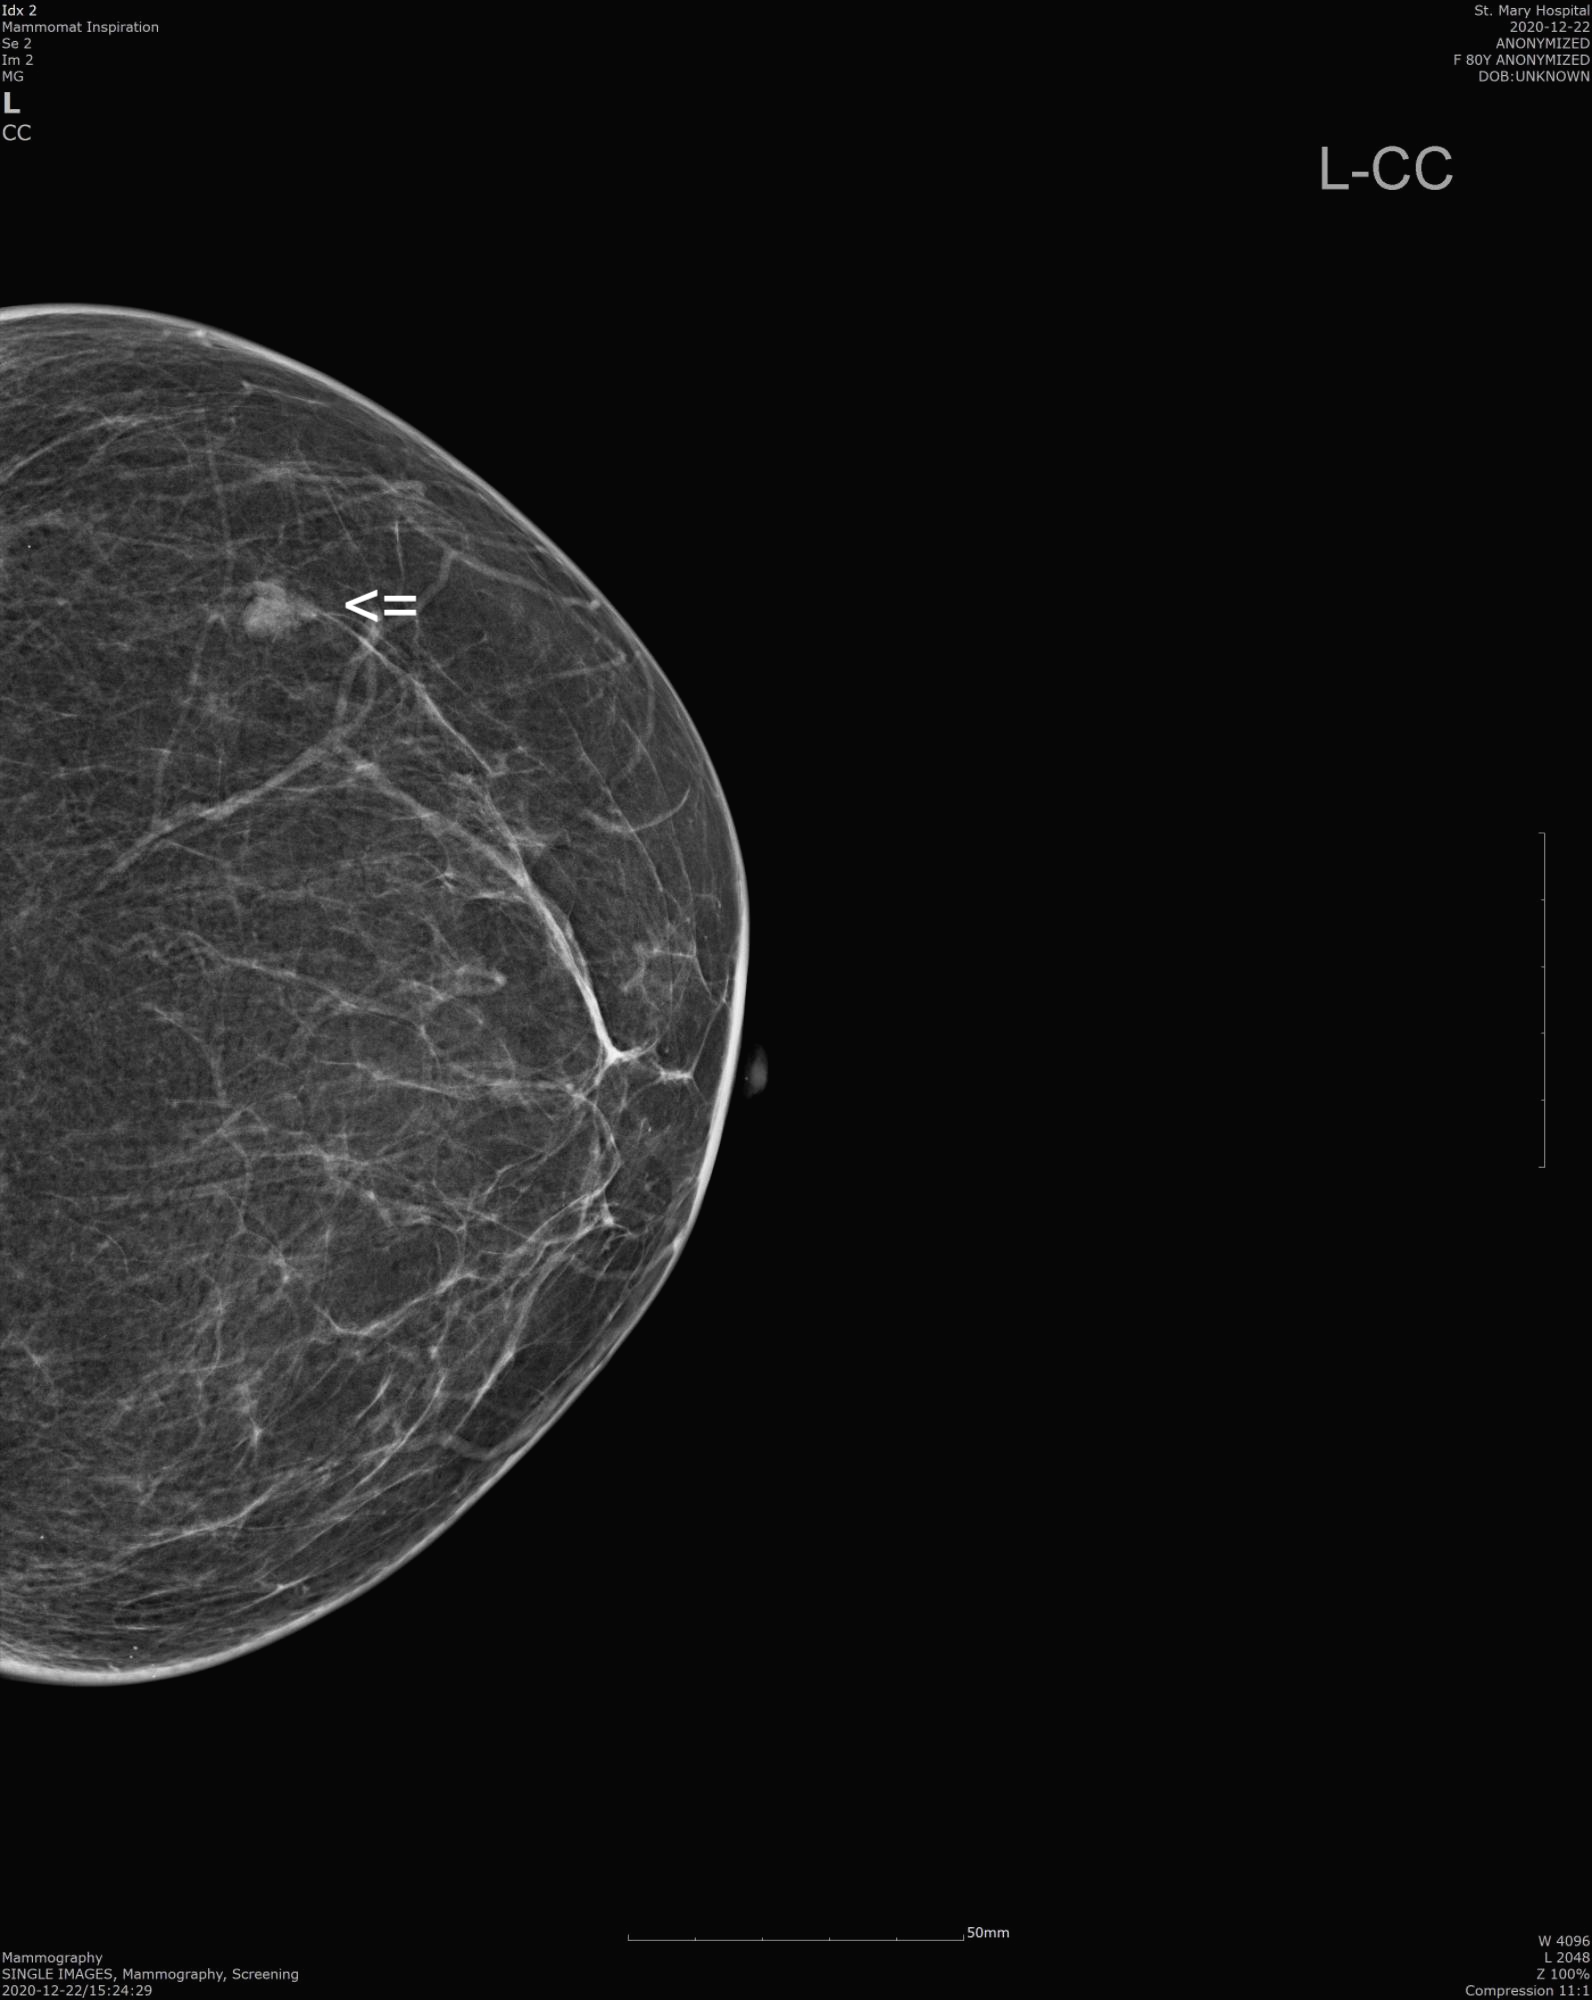

유방촬영상 좌측 유방 상외측(Left breast upper outer)에 작은 종양처럼 보이는 조직이 발견되어 정밀 검사를 권유받 제 외래로 오셨습니다.

저희 병원에서 2020.12.22일 유방촬영술, 유방초음파 검사를 시행했습니다.

[유방촬영술 판독]

There is asymmetrical obscured nodular shadow in left outer, upper portion

유방 좌측 화살표 한 부분에 작은 결절이 관찰됩니다.